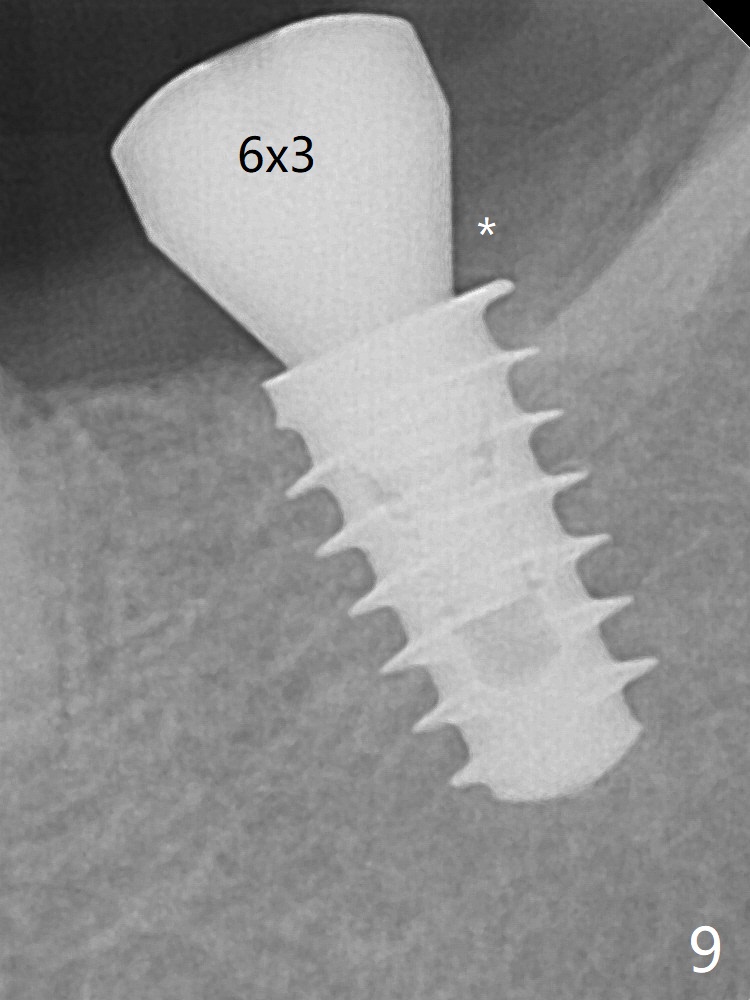

In fact, the mesial crest of the socket could be used as a more secure landmark (bony vs. soft tissue) for osteotomy depth (Fig.4 arrowhead) with drill stopper. To place the implant subcrestal, the initial osteotomy should be 1-2 mm deeper. When she returns 2 years 9 months postop, the wound has healed. The implant needs to be uncovered. Make sure to have clearance for a healing abutment. Use sensor 1 for PAs before and after uncover. The implant appears to be tilted distal. An angled abutment may be required. Take PA for seating confirmation. Guided surgery is preferable. The implant plateau is covered by the bone 2 years 9 months postop (Fig.8 *). The healing screw is removed with difficulty, while a 6x3 mm healing abutment is placed with resistance, probably related to interference from the distal crest (Fig.9 *). It is much easier with removal of the crest bone using surgical bur, because of clearance (Fig.10 *). It is the best to have a particular drill to remove the excess bone. There is no interference to insert and torque a 5x4(2) mm pair abutment 2 weeks post uncover (Fig.11). Due to poor trajectory (guide necessity) and tight proximal contact, the crown is not completely seated (Fig.12). However, the abutment screw is unlikely to get loose in the future.